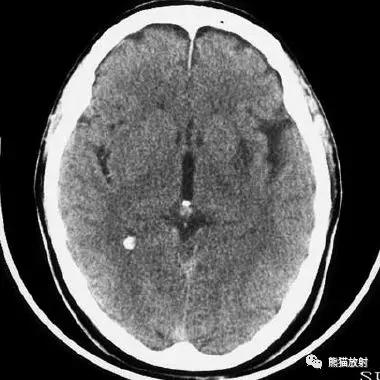

右侧基底节区脑梗死,增强后病灶看上去有所缩小。